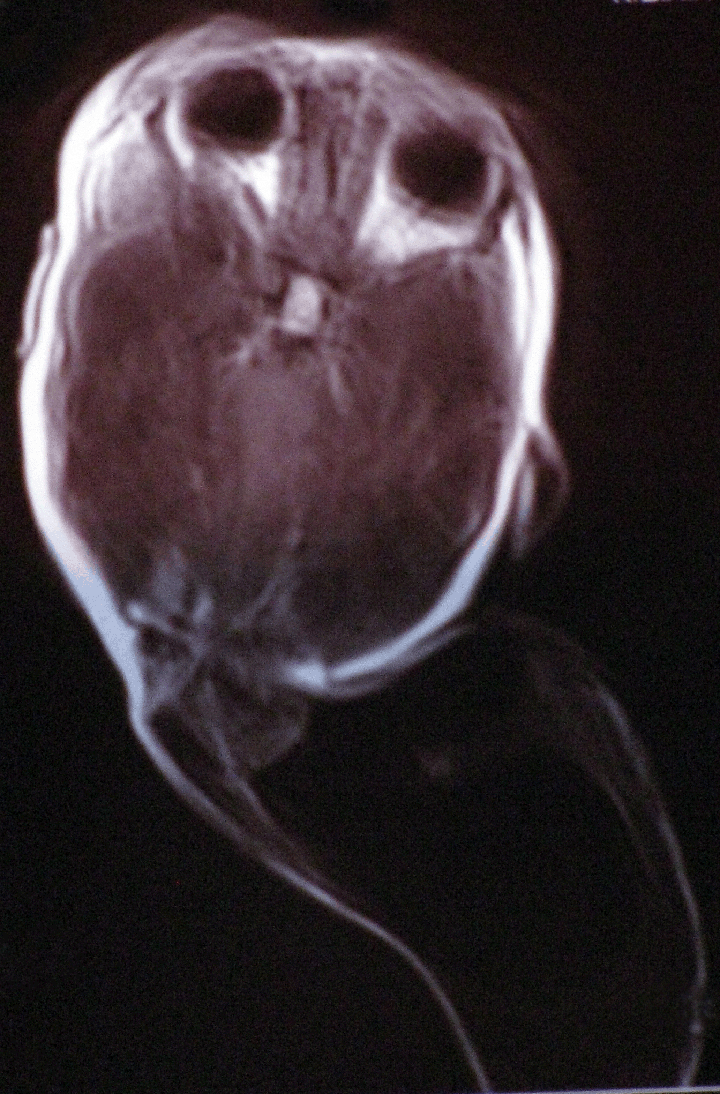

On preanesthetic evaluation, cardiovascular, respiratory and neurological system examination was normal. There was a swelling that measured 16x10 cm arising from posterior part of the head. No other congenital anomaly was detected. Magnetic resonance imaging (MRI) showed giant occipital meningoencephalocele with a minimal herniation of occipital lobe into the swelling (Figure 1).

Figure 1: MRI of the patient showing meningoencephalocele.